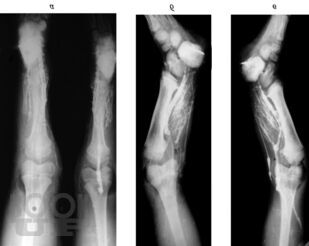

В монографии излагаются результаты многолетнихисследований, проведенныхв научно-исследовательском детском ортопедическом институте им. Г. И. Турнера. Рассматриваются вопросы клиники, диагностики и лечения врожденныхпороков развития костей голени у детей в возрасте от 3 мес. до 15 лет и старше. Описываются новые методики операций, основанные на сберегательной тактике, адекватные различным вариантам порока, позволяющие восстановить форму и функции конечности, техразновидностей порока развития костей голени, которые до настоящего времени считались неоперабельными и подлежали только ампутации. Монография предназначена для ортопедов, травматологов и хирургов.